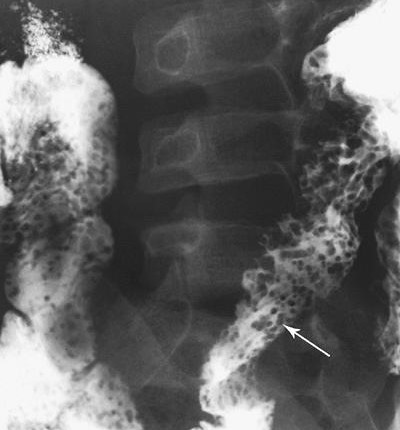

Viêm đại tràng do lao có hình ảnh giống bệnh Crohn, bệnh hiếm ở người da trắng nhưng hay gặp ở người châu Á và bệnh nhân AIDS. Mặc dù phần lớn là thứ phát sau lao phổi, nhưng đa số bệnh nhân không có bằng chứng lao phổi trước đó hoặc lao phổi hoạt động. Với bệnh nhân châu Á, phần lớn bệnh nhân lao ống tiêu hóa là do nuốt trực khuẩn lao bò. Chẩn đoán trực khuẩn kháng axit hoặc u hạt hoại tử bã đậu có độ nhạy thấp (khoảng 32% và 50%, tương ứng) [9]. Với sự hiểu biết tốt hơn về các đặc điểm của viêm lao đại tràng, chẩn đoán sớm bằng chụp cản quang kép là có thể [10]. Các đặc điểm sớm của lao đại tràng là co thắt, tăng tiết, tăng nhu động, tăng sản lympho, các nếp dầy, và các vết loét nông (Hình 18). Các dấu hiệu của viêm lao đại tràng tiến triển khi chụp cản quang kép bao gồm các vết loét ngang (Hình 19), các nốt, các nếp dầy, polyp viêm hoặc sau viêm, hẹp và biến dạng vùng hồi-manh tràng (Hình 20).

Hình 19. Bệnh nhân nữ 22 tuổi bị lao đại tràng giai đoạn tiến triển. Chụp cản quang kép bộc lộ các vết loét ngang và vết loét theo chu vi (mũi tên) ở vùng hồi-manh tràng và đại tràng lên.